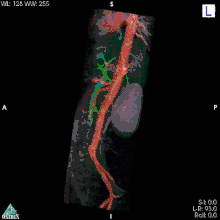

МР-ангіографія

Магнітно-резонансна ангіографія (МРА) — метод отримання зображення кровоносних судин за допомогою магнітно-резонансного томографа. Дослідження проводиться на томографах з величиною індукції магнітного поля не менш ніж 0,3 Тл. Метод дозволяє оцінювати як анатомічні, так і функціональні особливості кровотоку. МРА ґрунтується на відмінності сигналу рухомої тканини (крові) від сигналу навколишніх нерухомих тканин, що дозволяє отримувати зображення судин без застосування будь-яких рентгеноконтрастних засобів. Для отримання більш чіткого зображення застосовують особливі контрастні речовини на основі парамагнетиків (гадоліній).